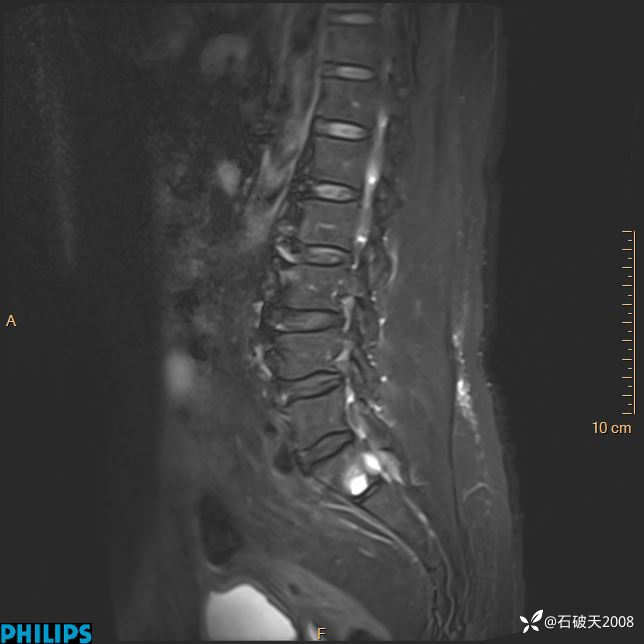

2023年3月份MRI影像

T2矢状位